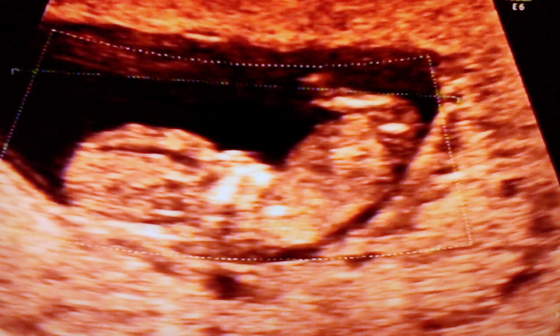

a to taki filmik naszej dzidzi robiony niestety komorka przez mojego malza wiec nie jest idealny

szkoda ze jak bylismy ostatnio to tak nie filmowal bo wtedy dzidzia sie duzo lepiej wystawiala